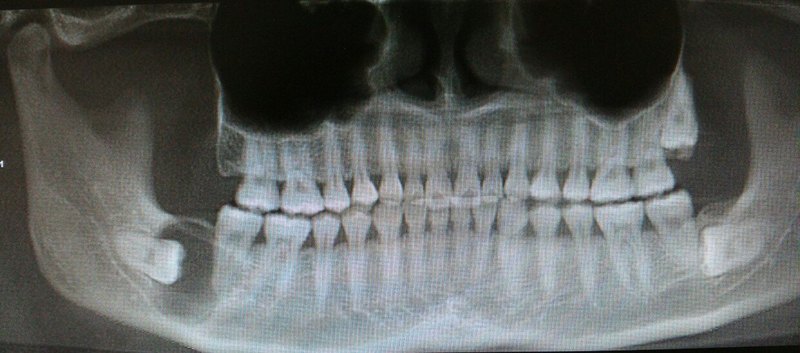

颌骨里的隐形“炸弹”